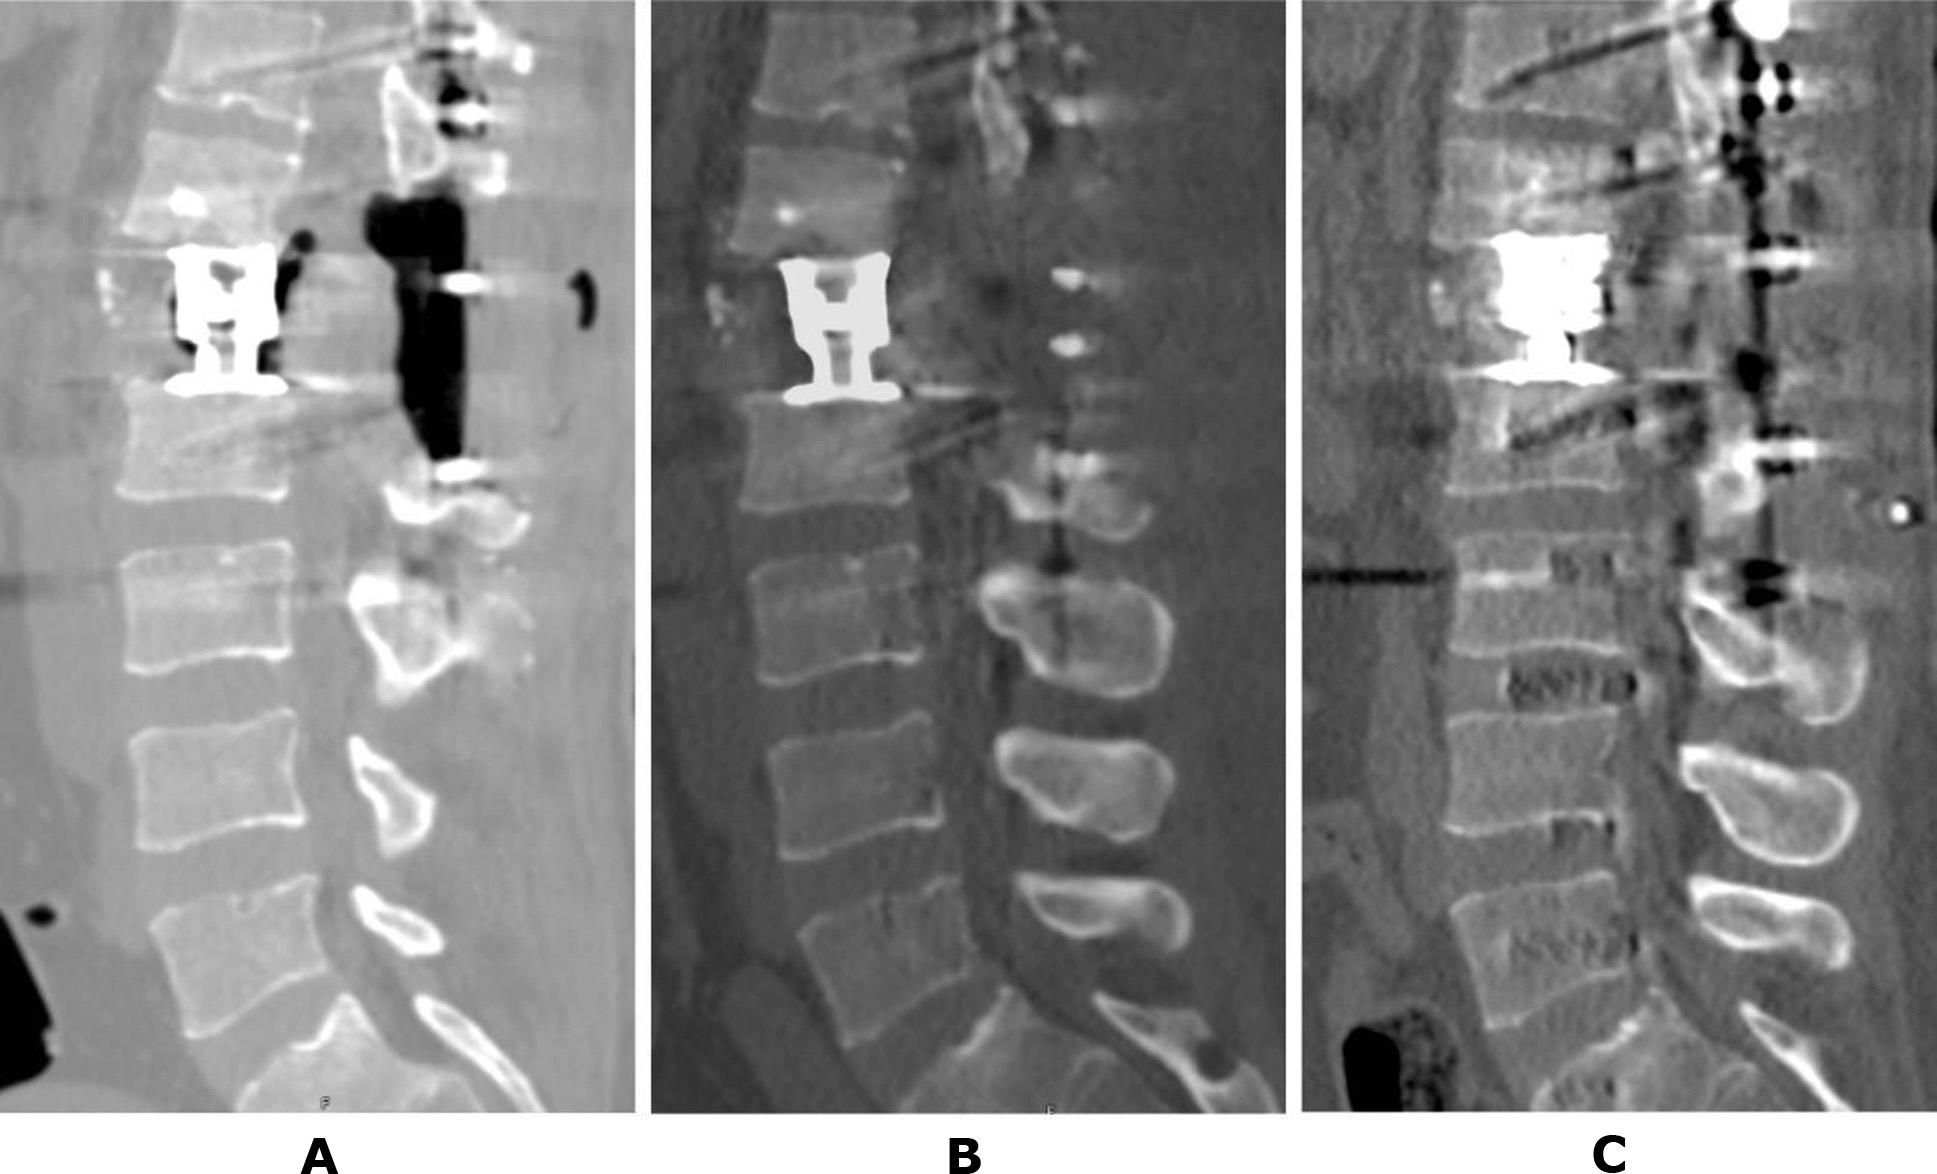

It is noteworthy that stabilization surgery in all patients with post-traumatic necrosis associated with unstable spinal injuries completely prevented further progression of destructive processes. None of the presented clinical cases involved the use of osteotropic antibacterial therapy, underscoring the aseptic nature of the condition. For example, consider the follow-up data of patient T. (Case No. 2). Amid total lysis of the L1 vertebral body, rapid destruction of the endplates of the adjacent vertebrae was observed (see Figures 2B, 2C). However, following decompressive-stabilization surgery—including removal of L1 vertebral body fragments, placement of a body-replacement implant via a posterior approach, and subsequent transpedicular stabilization of the Th11-Th12-L2-L3 vertebrae—the process was fully arrested (Fig. 4A). Follow-up studies conducted 2 and 6 months after surgery demonstrated stable fixation and no signs of progressive osteolysis (Figures 4B, 4C).

Fig. 4. Patient T., 41 years old. CT scan of the lumbar spine: A – 3 days after surgery; B – 2 months later; C – 6 months later (details provided in the text)